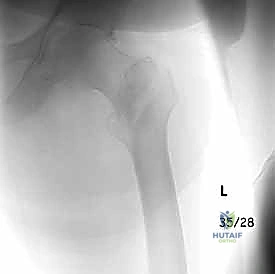

التصوير الطبي المتقدم

- الأشعة السينية (X-rays): هي المعيار الذهبي الأولي. يتم أخذ صور من الأمام للخلف (AP) وصور جانبية (Lateral) للحوض والورك المصاب. تكشف هذه الصور عن موقع الكسر، نوعه (بسيط أم مفتت)، ودرجة الإزاحة.